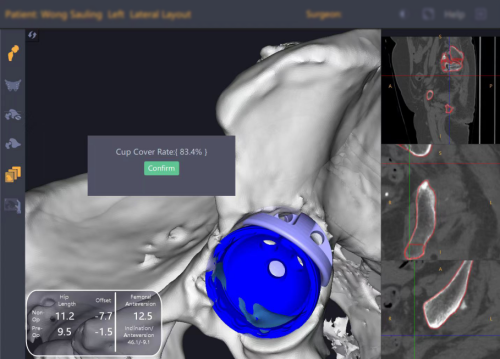

从规划到执行,全程数据支撑

术前,团队基于患者CT影像,在锟铻®系统中完成膝关节三维重建,制定个性化截骨方案,针对关节外畸形力线娇正难题,精确计算矫正角度与假体型号。术中,机器人通过光学导航实时追踪骨骼位置,动态监测关节屈伸间隙,医生根据系统反馈即时调整操作,确保软组织平衡与力线精准复位。